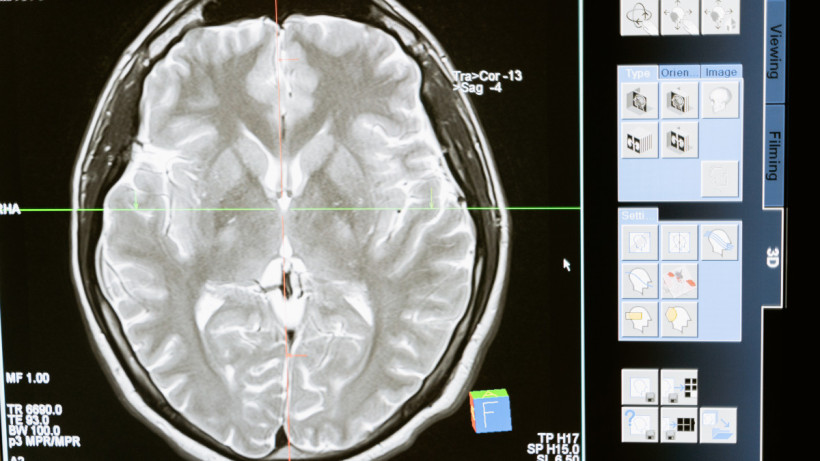

© Pexels.com

Фото: © Pexels.com